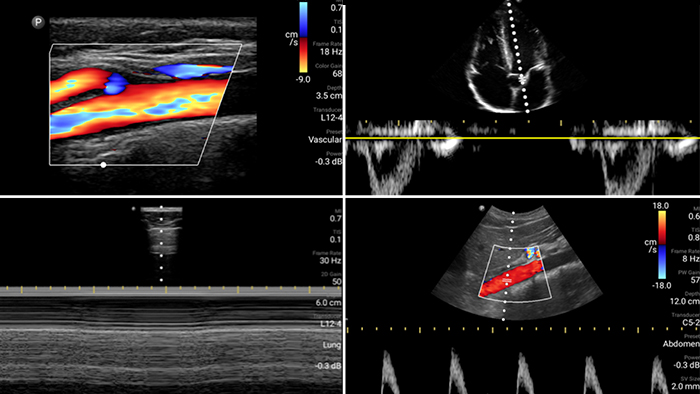

Evaluate, diagnose and treat your patients in minutes with a multi-point POCUS exam.

See for yourself Get the full picture with clear whole-body imagery for a fast, accurate response during an emergency.

Lumify transducers for emergency medicine

Lumify L12-4 broadband linear array transducer

Lumify S4-1 broadband phased array transducer

• 4 to 1 MHz extended operating frequency range • 2D, color Doppler, M-mode, advanced XRES and multivariate harmonic imaging • High-resolution imaging for abdominal and cardiac applications: Cardiac, OB/GYN, Lung, Abdomen and FAST imaging preset optimizations Lumify aids life-saving technology in prehospital setting

Focused Assessment with Sonography in Trauma (FAST) exam